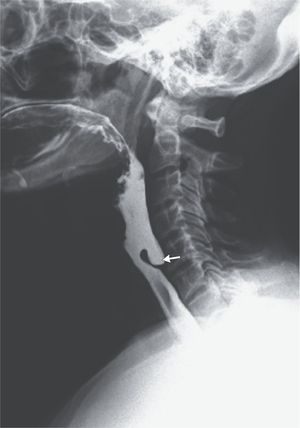

A 67-year-old man presented to the gastroenterology clinic with an 8-month history of progressive dysphagia, weight loss, regurgitation, and halitosis. A physical examination revealed no palpable cervical mass. Laboratory studies showed a moderately low serum albumin level. A barium swallow examination showed stasis of barium in the upper esophagus with an outpouching lesion anterior to the C5 and C6 vertebrae (arrow). Upper gastrointestinal endoscopy revealed a pharyngoesophageal diverticulum, or Zenker’s diverticulum. Zenker’s diverticula are herniations of the hypopharynx through a defect in Killian’s triangle, an area bound by the inferior pharyngeal constrictor muscles and cricopharyngeus muscles. These diverticula are thought to result, in part, from abnormalities of the upper esophageal sphincter. Small diverticula can be asymptomatic and left untreated, whereas large diverticula can result in dysphagia, regurgitation, chronic aspiration, or cough, and surgery may be warranted. In this patient, an endoscopic Zenker’s diverticulectomy was performed. Within 3 days after the surgery, the dysphagia, regurgitation, and halitosis had resolved, and the patient remained asymptomatic at a follow-up visit 8 months later. Source: nejm.org